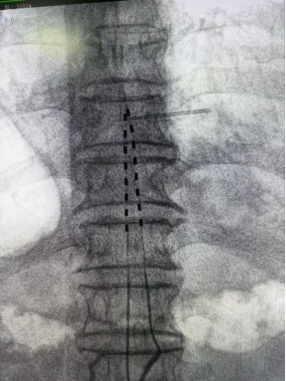

经过详尽的术前准备,并向龙嗲详细解释手术原理,李勇辉团队随即为患者安排了一期微创手术,术后即刻返回病房,为龙嗲开机测试,并调整参数,疼痛区域被温和酥麻感替代,NRS评分降至2-3分。

一期测试:手术微创,费用较低,在DSA引导下电极植入,7天刺激器外挂测试,疼痛缓解>70%;